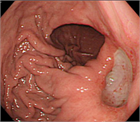

1. 難渋例の症例について画像を用いて解説した。